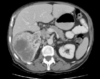

TOMOGRAFIA DE ABDOMEN COM CONSTRASTE VENOSO .

MASSA RETROPERITONEAL A DIREITA QUE COMPRIME AS VISCERAS A DIREITA , A QUAL NÃO INVADE AS ESTRUTURAS. PRESENÇA DE CAPTAÇÃO HETEROGENEA DO CONSTRASTE NA PERIFERIA

ASPECTO DE SARCOMA PERITONEAL.